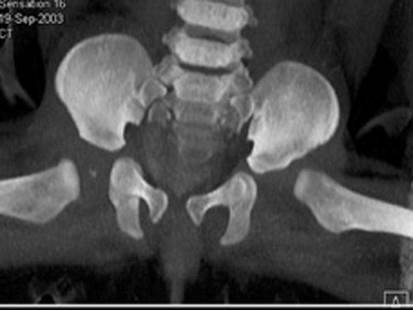

问题 男,3岁,走路跛行,两下肢不等长,左脚外展受限,结合图像,最可能的诊断是 ( )

选项 A、先天性髋内翻 B、髋关节结核 C、髋关节后脱位 D、髋关节中心脱位 E、髋关节前脱位

答案 C